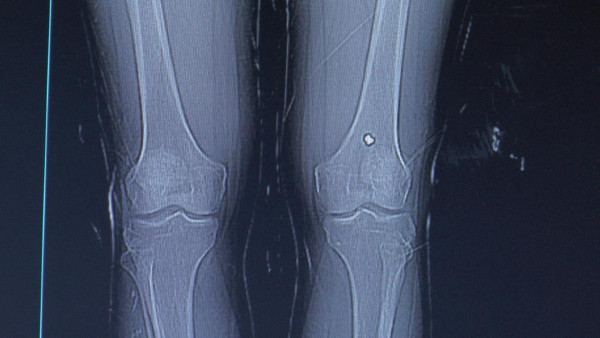

NEVŞEHİR'de bacağından tüfekle vurulan şahıs, tedavisinin ardından taburcu edildi. Olaydan 13 gün sonra şikayetleri artınca tekrar hastaneye giden şahsın diz kapağında mermi olduğu anlaşıldı.

Abone olEdinilen bilgiye göre olay, İbrahim Paşa Mahallesinde meydana geldi. Kenan Değerlier, A.S. ile tartışmaya başladı. Tartışmanın büyümesiyle A.S. 'havalı' tabir edilen tüfekle Kenan Değerlier’e ateş etti. Diz kapağından yaralandığını fark eden Değerlier, durumu polis ve sağlık ekiplerine bildirdi. Yaralı hastaneye kaldırılarak tedavi altına alındı. Acil serviste ilk müdahalesi yapılan Kenan Değerlier, ardından taburcu edildi. 13 gün sonra diz kapağındaki ağrıların artmasıyla yeniden hastaneye müracaat eden Değerlier, burada hayatının şokunu yaşadı. Değerlier’in diz kapağında mermi olduğu anlaşıldı. Ortopedi polikliniğine sevk edilen şahsın diz kapağındaki mermi ameliyatla alındı.